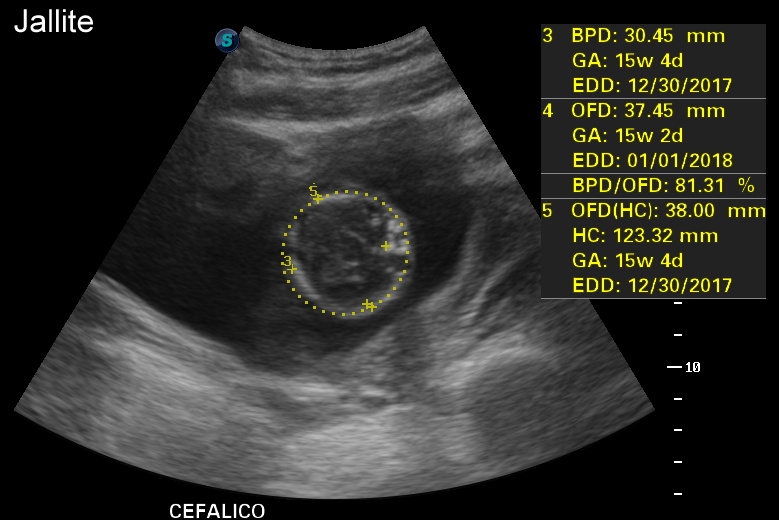

Ecografia 2D 11 semanas Higroma quistico pliegue nucal patologico Dr. Rafael Ortega Muñoz

HIGROMA QUISTICO MEDICINA FETAL PERÚ YouTube

Higroma quístico del primer trimestre Diagnóstico de hernia diafragmática congénita